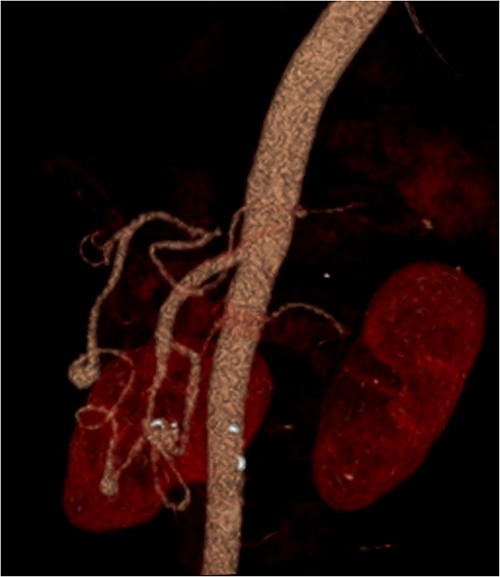

A multiphase CT of the pancreas had unexpected findings. There were no pancreatic masses on the arterial and portal phase study, and no paraaortic or mesenteric lymphadenopathy. The abnormal calcification seen on the previous study corresponded to a dilated vessel along the superior margin of the pancreatic body. This dilated vessel was an abnormal communication between a tortuous ecstatic gastroduodenal artery and the first branch of the SMA, a Buhler’s arc communication. The celiac axis origin was narrowed >90%. No other suspicious solid organ mass lesion was identified. Soft tissues were unremarkable (Figs 5–8).

Multiphase CT pancreas, axial view demonstrating abnormal communication between the CA and the SMA.

Multiphase CT pancreas, coronal view: the gastroduodenal artery, off the common hepatic, communicating with the first branch of the SMA.

Multiphase CT pancreas, sagittal view: abnormal communication between the CA and the SMA. The celiac axis is markedly narrowed, >90%.

3D reconstruction demonstrating abnormal communication between the CA and SMA.